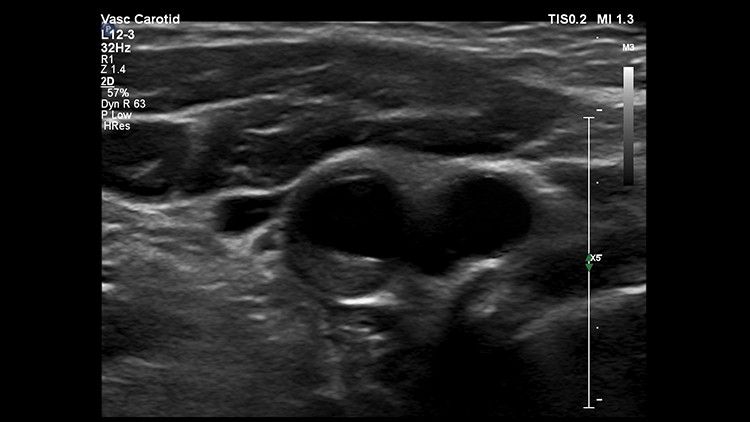

Педиатрический датчик PureWave

Создан специально для достижения более высокой детализации, позволяющей уверенно диагностировать даже самых маленьких пациентов. Датчик C9-2 для системы EPIQ CVx является первым датчиком PureWave для педиатрии, который предлагает широкий спектр возможностей визуализации для новорожденных, грудных детей и взрослых пациентов. Особенностью этого датчика является кнопка "ишемический суб-режим", которая позволяет быстро и легко оценить коронарные артерии.